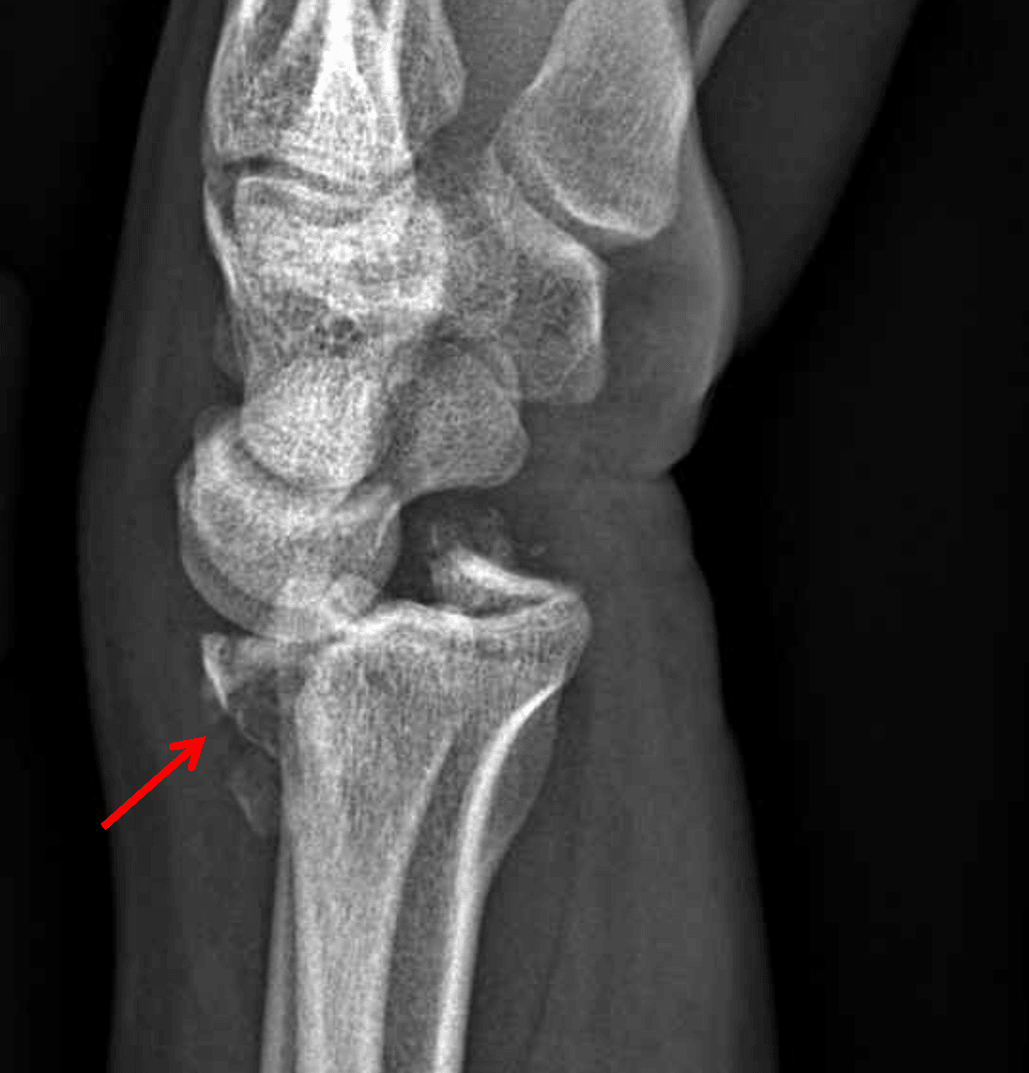

Barton fracture with dorsal displacement (red arrow).